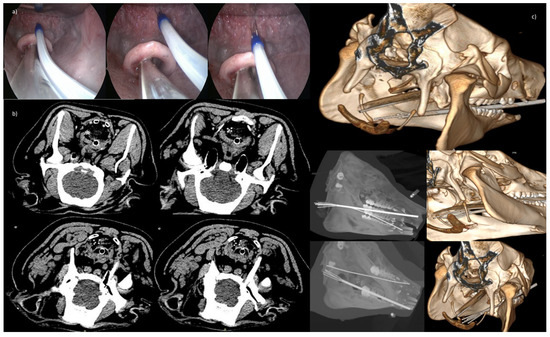

2.3.2. Endoscopic Trans-Oral and Trans-Anal Approach

2.4. Imaging Data Analysis